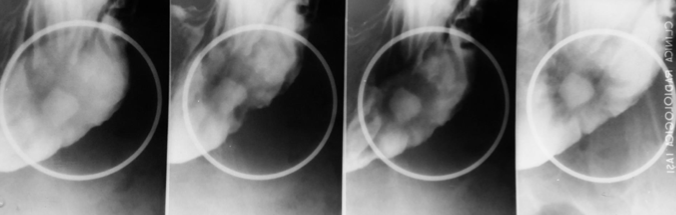

Diverticul Zenker